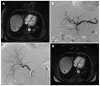

Unresectable primary and secondary liver malignancies present a major problem in the treatment of solid tumors. Transarterial radioembolization (TARE) is an increasingly used technique for treating various types of malignant liver tumors. This approach is appealing, as the mechanism of action is independent from other loco-regional treatments and potentially complementary to systemic therapies. There are two commercially available products in use for TARE: (90)Y-resin and (90)Y-glass microspheres. Currently available data indicates TARE so be safe and effective in hepatocellular carcinoma (HCC) and metastatic liver disease. In HCC the results compare well with chemoembolization, while the role of TARE in combination with kinase inhibitors has yet to be established. Current data on TARE in metastatic liver disease is promising, but there is a strong need for prospective randomized trials comparing TARE and modern chemotherapeutic regimen to support the growing role of TARE in metastatic liver disease.